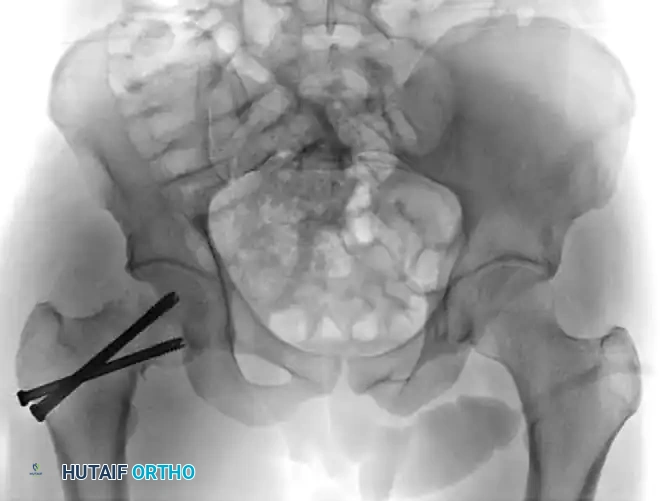

Figure: Anteroposterior radiograph demonstrating a severe varus malreduction of a femoral neck fracture following initial cannulated screw fixation.

Figure: Anteroposterior radiograph revealing an established nonunion of the femoral neck with hardware failure and backing out of the cannulated screws.